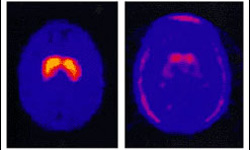

|  |  |  |  | MRI scan of (left) a healthy brain, and a that of a Parkinson sufferer. Could stem cells be used to treat such degenerative disorders effectively? | More and more of us are suffering from incurable diseases such as Parkinson's and Alzheimer's in which our nervous systems are degenerating.

Stem cells offer a lifeline for these patients, as they can be turned into replacement neurons to be transplanted into diseased brains.